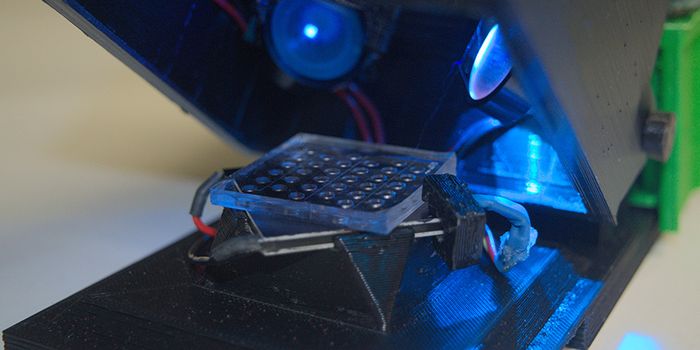

SEP 02, 2024Genetics & GenomicsMicroplate readers play a crucial role in the life sciences and biotechnology industry due to their ability to measure b ...